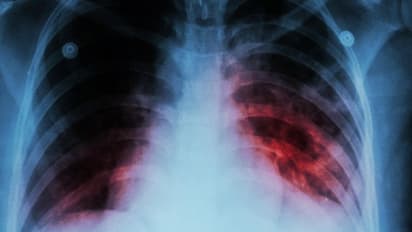

ബാക്ടീരിയ മൂലം പടരുന്ന രോഗമാണ് ടിബി. ഇത് ശ്വാസകോശത്തെയാണ് ബാധിക്കുന്നത്. ചികിത്സയിലൂടെ രോഗത്തെ പൂര്ണമായും ഭേദപ്പെടുത്താൻ ഇന്ന് സാധിക്കും. എങ്കിലും മരണനിരക്ക് വര്ധിക്കുന്നുവെന്നത് ആശങ്കയുണ്ടാക്കുന്ന വസ്തുതയാണ്.